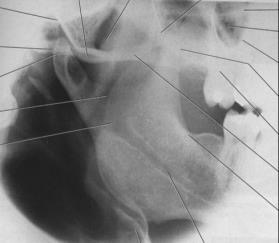

Lateral jaw: ramus of mandible

Purpose of the lateral jaw: body of the ramus

used to avaluate impacted teeth and fractures that extend to the ramus

the lateral jaw: ramus of the mandible is ideal for

Patients who cannot tolerate intraoral films, when pano images are not available